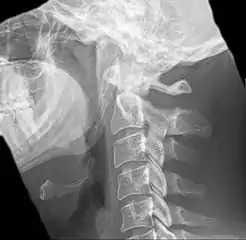

Radiograph, lateral view showing elongated stylohyoid process and stylohyoid ligament ossification

Radiograph, lateral view showing joint-like formation in ossified stylohyoid ligament

Imaging is important and is diagnostic. Visualizing the styloid process on a CT scan with 3D reconstruction is the suggested imaging technique.[12] The enlarged styloid may be visible on an orthopantogram or a lateral soft tissue X ray of the neck.